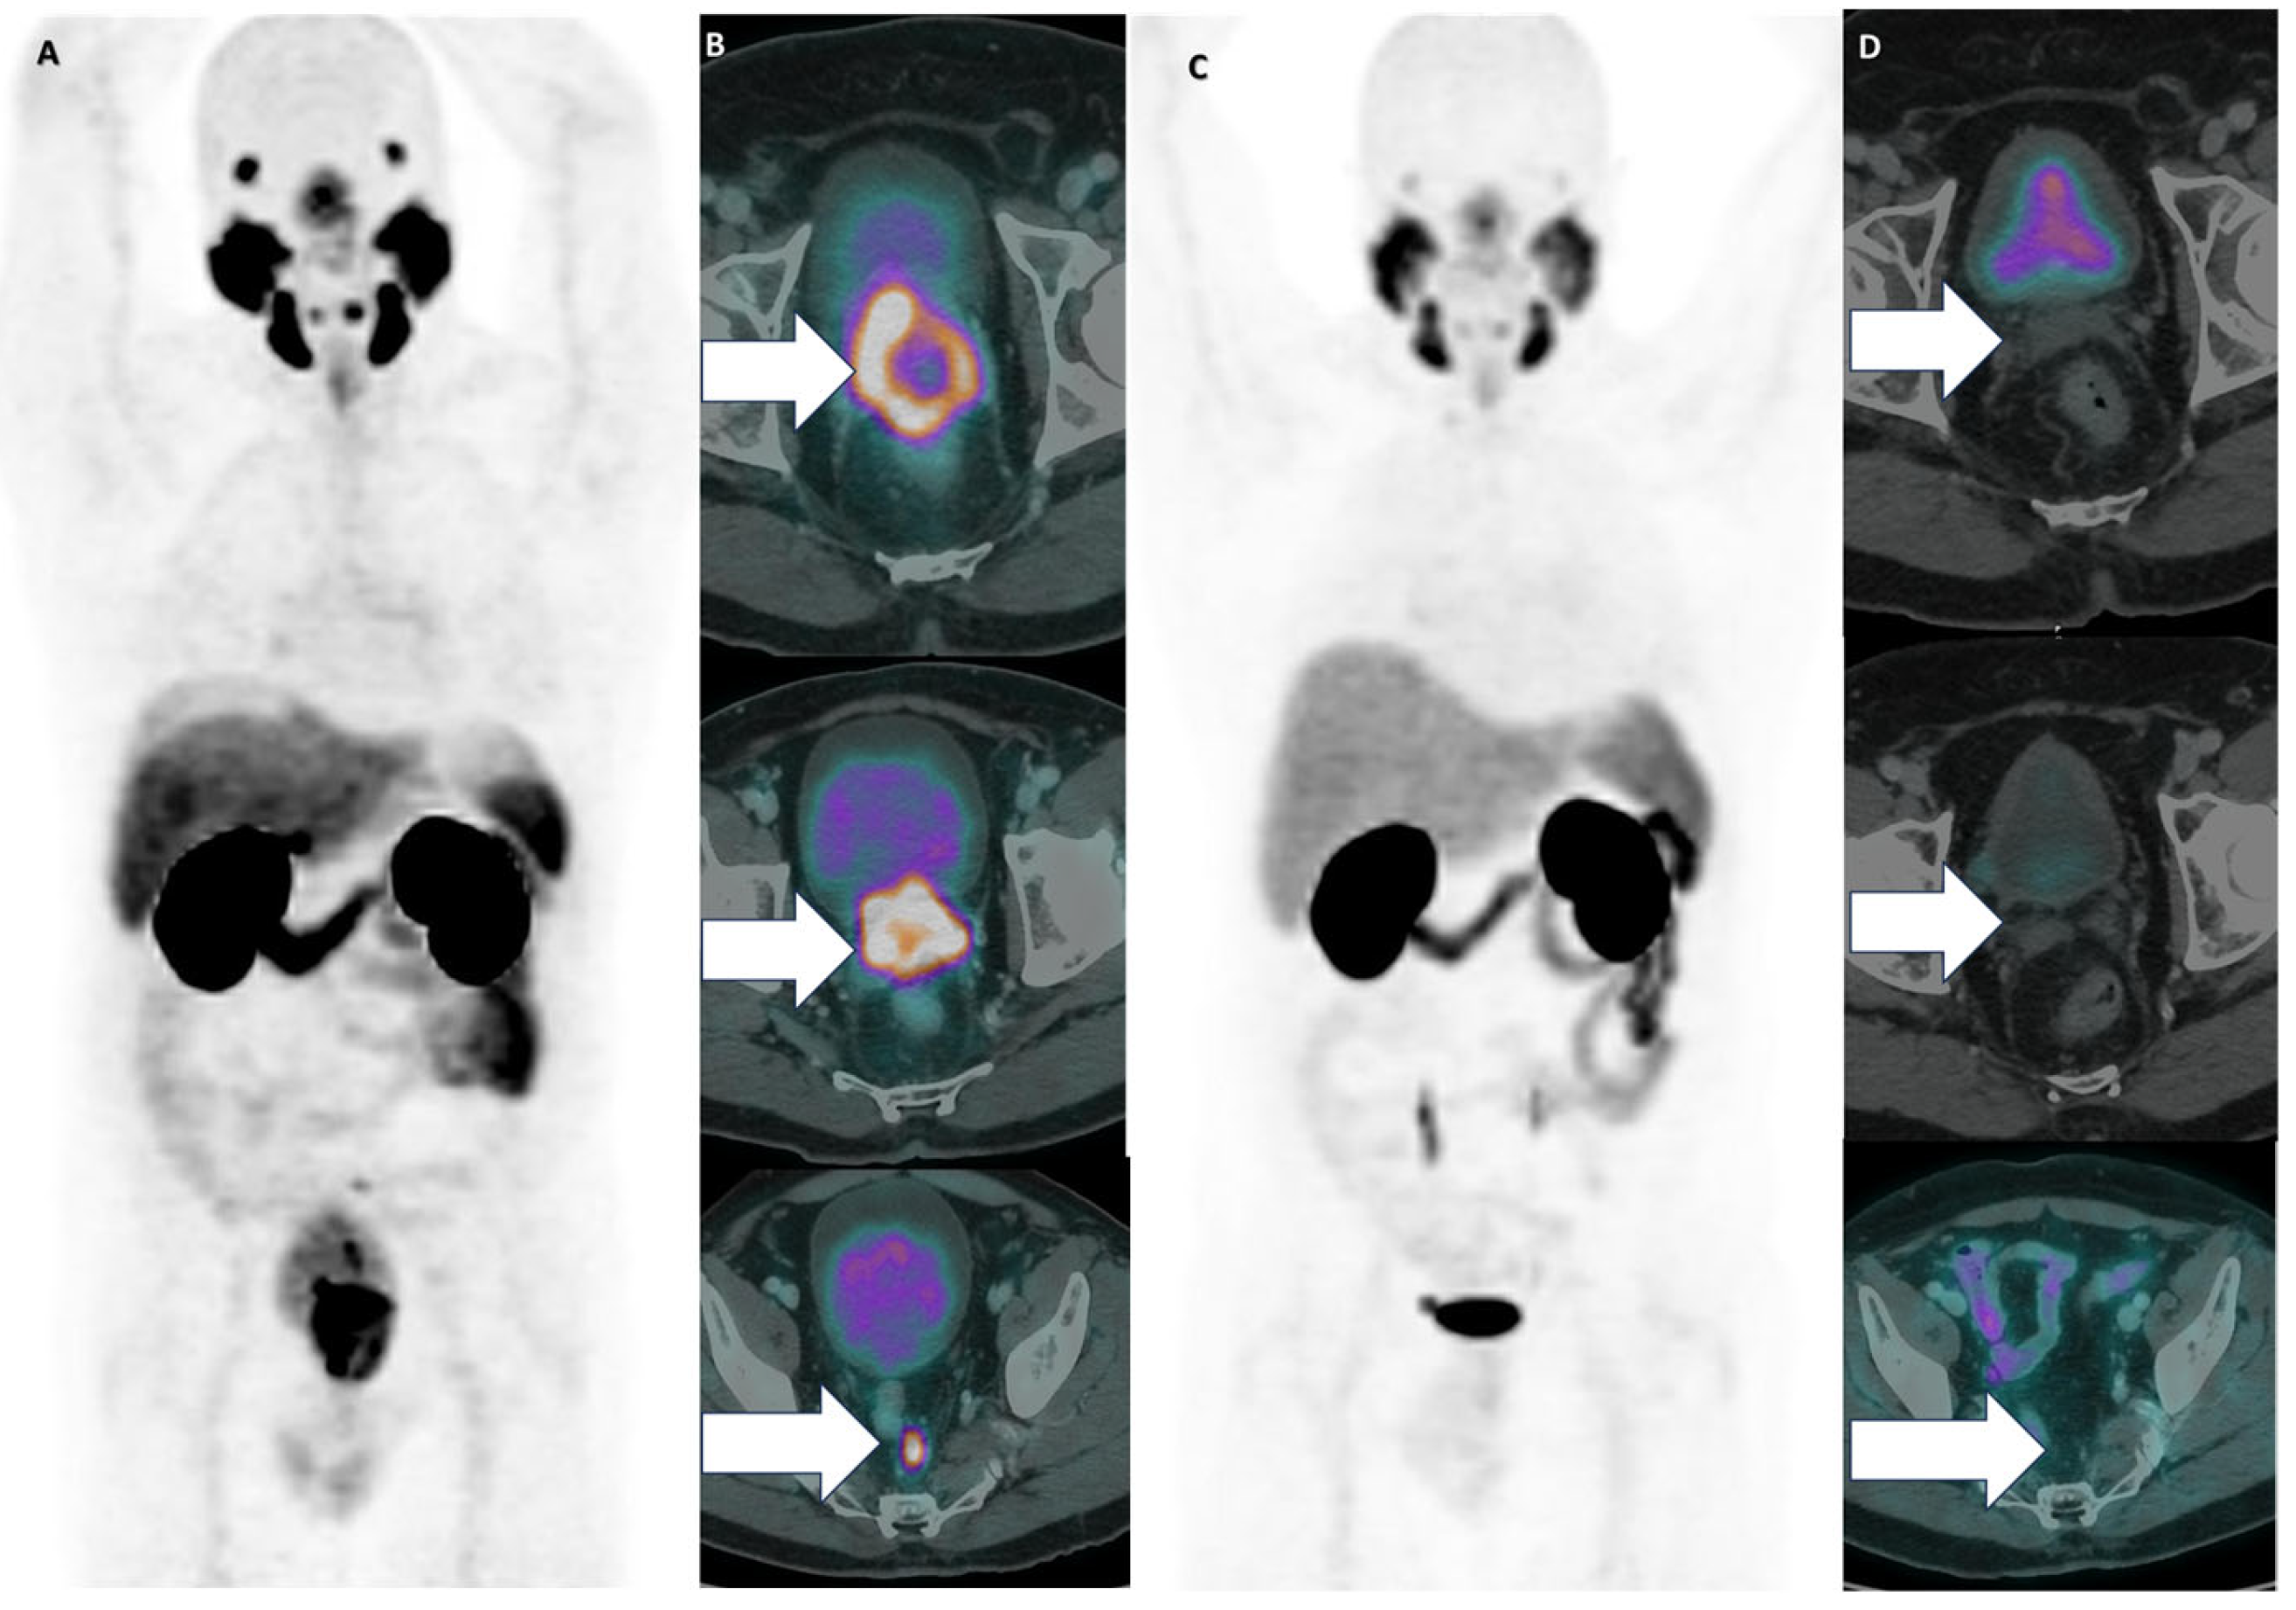

3. Results

| Prostatectomy, Salvage EBRT of Prostate Bed and Pelvic Lymph Pathways, Leuprorelin, Apalutamid, Darolutamid | 8 | LNM | 2 | 19 | −683 |